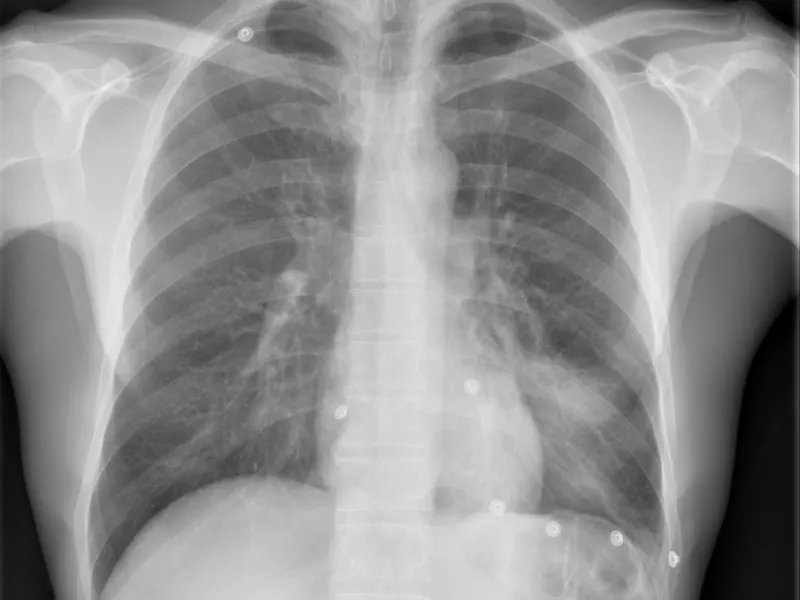

Consolidación del lóbulo medio – Signo de la silueta positivo

Consolidación del lóbulo medio – Signo de la silueta positivo Presentación Edad: N/A Género: Femenino…